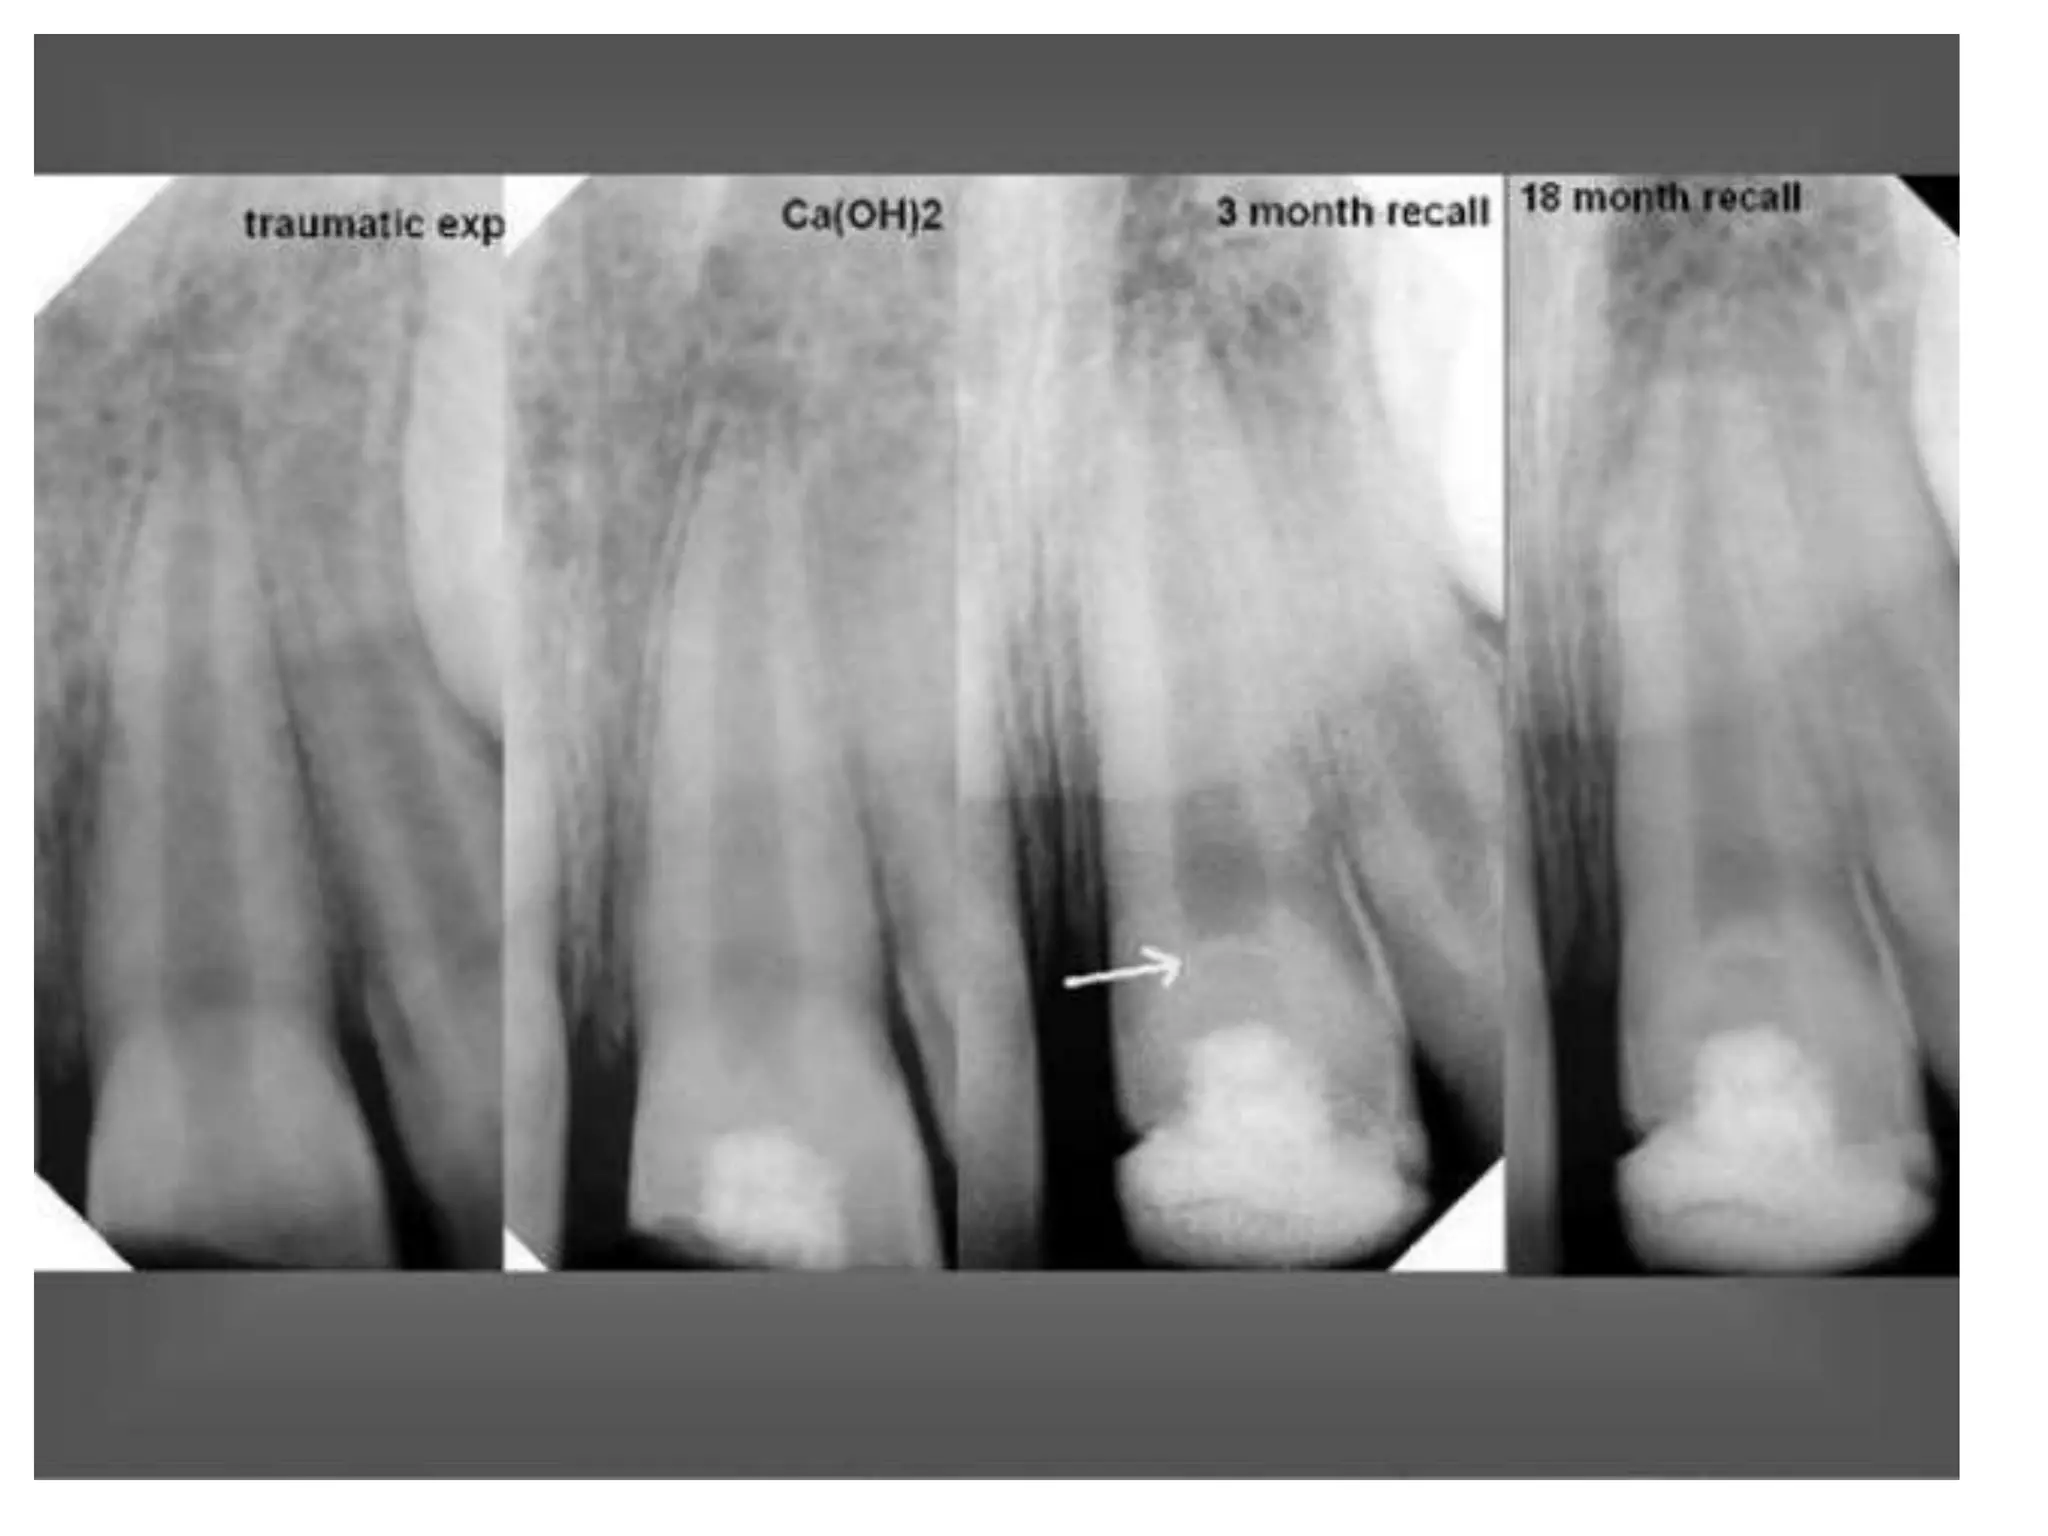

Apexogenesis and apexification are treatments relevant to the trauma of maxillary central incisors, which are frequently injured in children. The highest instance of such trauma is observed between the ages of 8 and 10. There is an exploration of new strategies for treating teeth with an open apex.